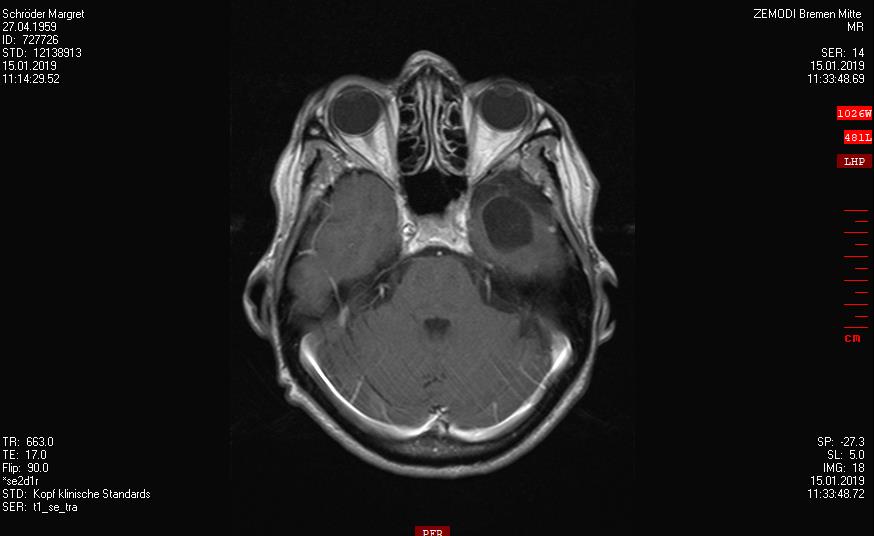

2019-2020

Ein Rezidiv wächst langsam

Die Tumorkonferenz vom Krankenhaus Bremen-Mitte rät zum Abwarten.

Der beratende Arzt dort, findet eine Bestrahlung im Gamma-Knife nicht falsch.